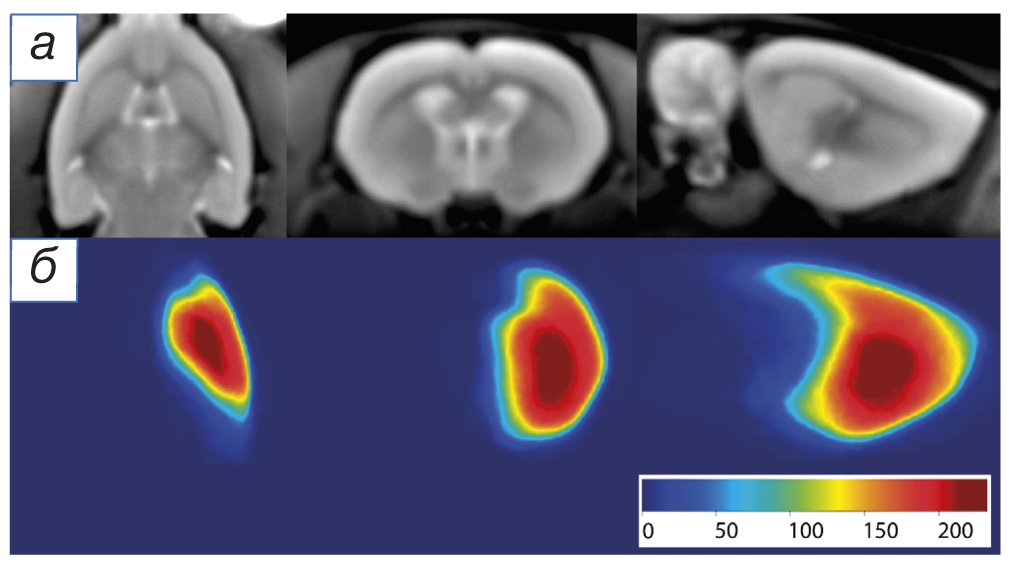

Fig. 1. An example of cerebral infarction segmentation using artificial intelligence: a — T2-weighted images in the axial, frontal and sagittal planes (from left to right), in which a hyperintense lesion of cerebral infarction is visualized in the right hemisphere; b — automatic segmentation of the lesion of cerebral infarction (marked in red).

In order to compile an atlas of the blood supply systems of the intracranial branches of the internal carotid artery according to MRI data, we have used an artificial intelligence system, allowing for significant segmenting the cerebral infarction zone after the occlusion of the medial cerebral artery (Fig. 1). The obtained results of segmenting the experimental cerebral infarction were registered in a unified coordinate space using the rat brain template (Fig. 2, a). Based on the obtained segmentation files, summarized in a single coordinate system, the thermal maps of the rates of developing the cerebral infarction foci were compiled (see Fig. 2, b).